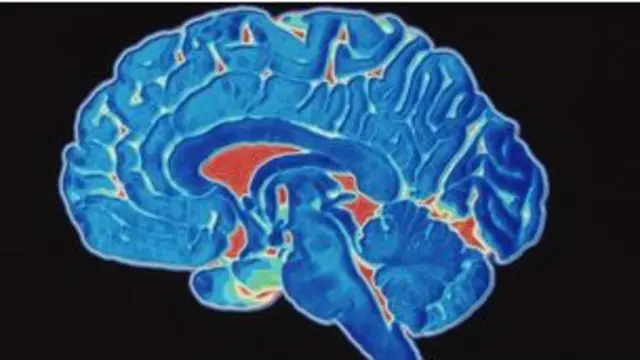

خلايا العين يمكن أن تساعد في تشخيص مرض الزهايمر

أكد العلماء أن التغييرات التي تطرأ على خلايا معينة في شبكية العين قد تساعد في تشخيص ومتابعة تطور مرض الزهايمر(العتة) .

وقال العلماء إن "فقدان الخلايا العصبية لشبكية العين قد يكون له صلة بفقدان خلايا المخ جراء مرض الزهايمر، كون شبكية العين هو امتداد مباشر من الدماغ".